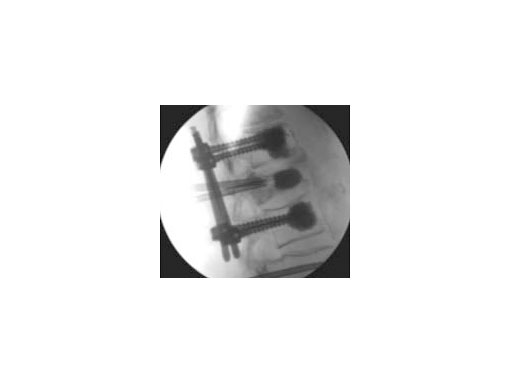

Synflate can be used stand-alone or in combination with posterior instrumentation (see the clinical cases within this article).

A 78-year-old woman was affected by steroid induced osteoporosis. She had persisting pain (mechanic and muscular) due to static imbalance (hyperkyphosis) and nonunion 8 months after a minor trauma with a vertebral compression fracture and vertebra plana of L1, and development of symptomatic stenosis of the spinal canal with loss of mobility over time. Pre-existing degenerative lumbar scoliosis was increased by the fracture.